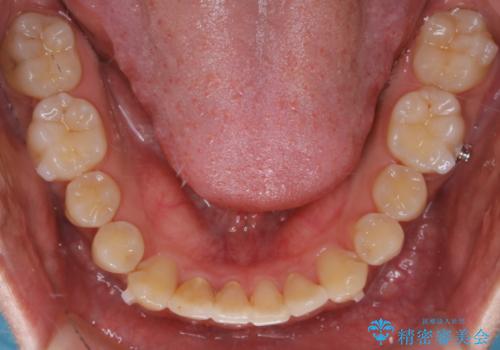

- 前歯のがたつきが気になるとご相談にいらした方です。左の奥歯の噛み合わせのズレも認められたため、インビザライン治療にて改善しました。

主訴である前歯のガタつきだけでなく、奥歯の噛み合わせからしっかり治療したため、治療期間が長めとなりました。患者様ご本人としては治療の途中で一時的にモチベーションが下がったこともあったようですが、最後まで頑張って続けて頂けたことで噛み合わせ及び見た目の改善を行うことが出来ました。